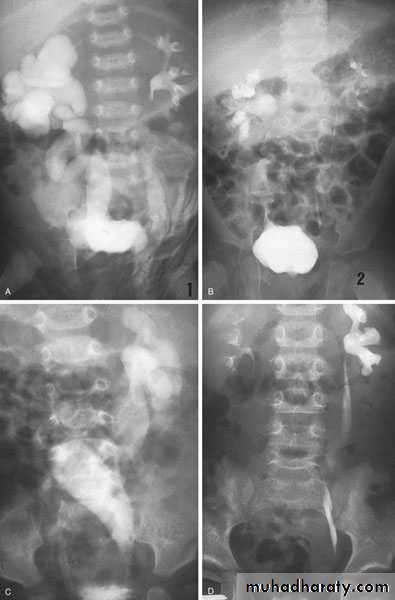

Ureteroceles

Is due to congenital atresia of the ureteric orifice which causes a cystic dilatation of the intramural portion of the ureter

IVU, cystoscopy, cystogram

The ‘adder head’ on excretory urography

is typical.

Cobra (Adder) head appearance of ureterocele

Ureterocele involving single system Ureterocele involving duplicated ureter

Congenital Megaureter

Grossly dilated ureterUnilateral or bilateral

Diagnosis : IVU

Postcaval (Retrocaval) ureter (Preureteral Vena Cava )

The right ureter pass behind the inferior vena cavaThis might causes obstruction

Diagnosis: IVU